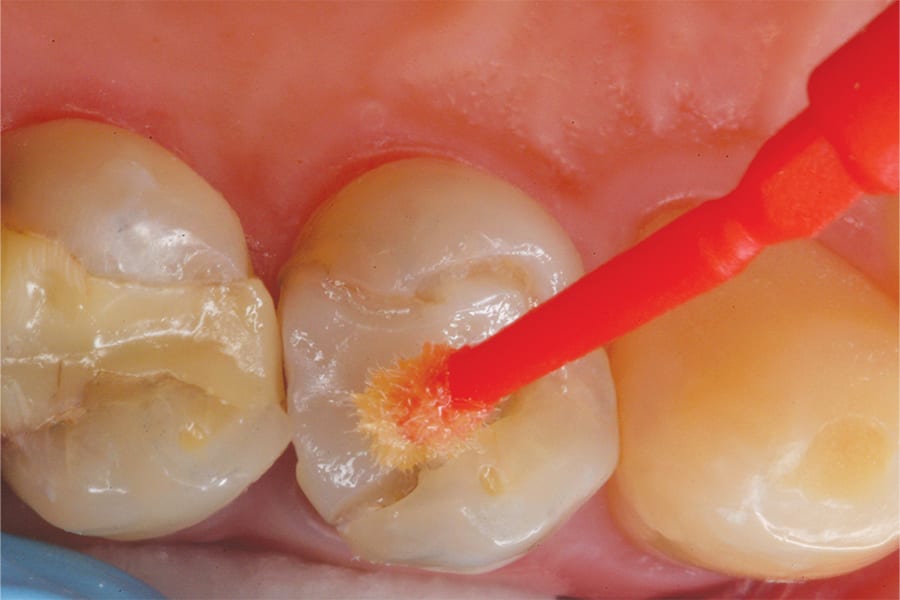

After the perimeter preparation was complete, it was inspected for any remaining decay. Microabrasion was then performed on the preparation to increase the bondability of the old composite surfaces (Figure 3).1 With the preparation complete, an adhesive (BeautiBond®, Shofu) was applied, thoroughly air-dried, and light cured for 3 to 5 seconds with a LED curing light (Figure 4 through Figure 6). This adhesive was selected for its one-step, self-etch formula, which simplifies bonding procedures by eliminating the need for multiple systems. It features dual-adhesive monomers that deliver predictable, strong, and reliable bonds to both enamel and dentin, and with its extremely low film thickness of less than 5 µm, it helps eliminate marginal stain lines.